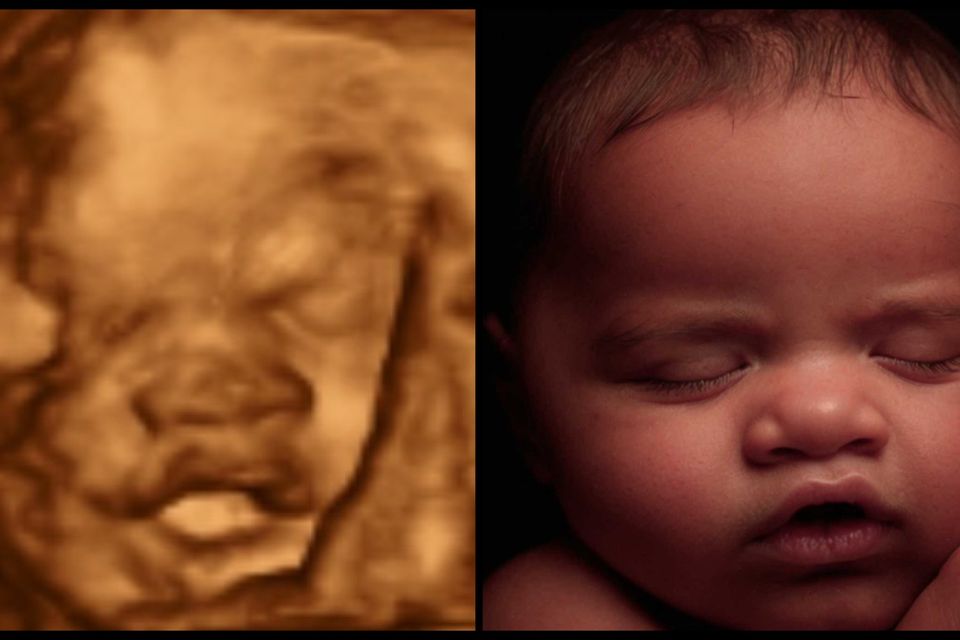

Most Realistic & lifelike photo you can get until the arrival of your little one. Using the newest technology to change your 3d/4d photo into something more realistic without changing any of your baby's features.